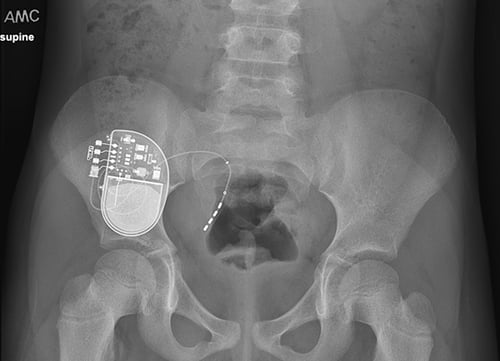

Sacral neuromodulation is a minimally-invasive surgery where a device the size of a watch is placed in the upper portion of the buttock. The device, known as an InterStim, is connected to an implanted wire near the sacral nerves. The sacral nerves are what regulate the function of the bladder and bowel.

Sacral neuromodulation is a minimally-invasive surgery where a device the size of a watch is placed in the upper portion of the buttock. The device, known as an InterStim, is connected to an implanted wire near the sacral nerves. The sacral nerves are what regulate the function of the bladder and bowel.

The InterStim device sends mild electrical impulses to the sacral nerves to help normalize their function and achieve better communication, thereby normalizing the function of the bladder and colon.